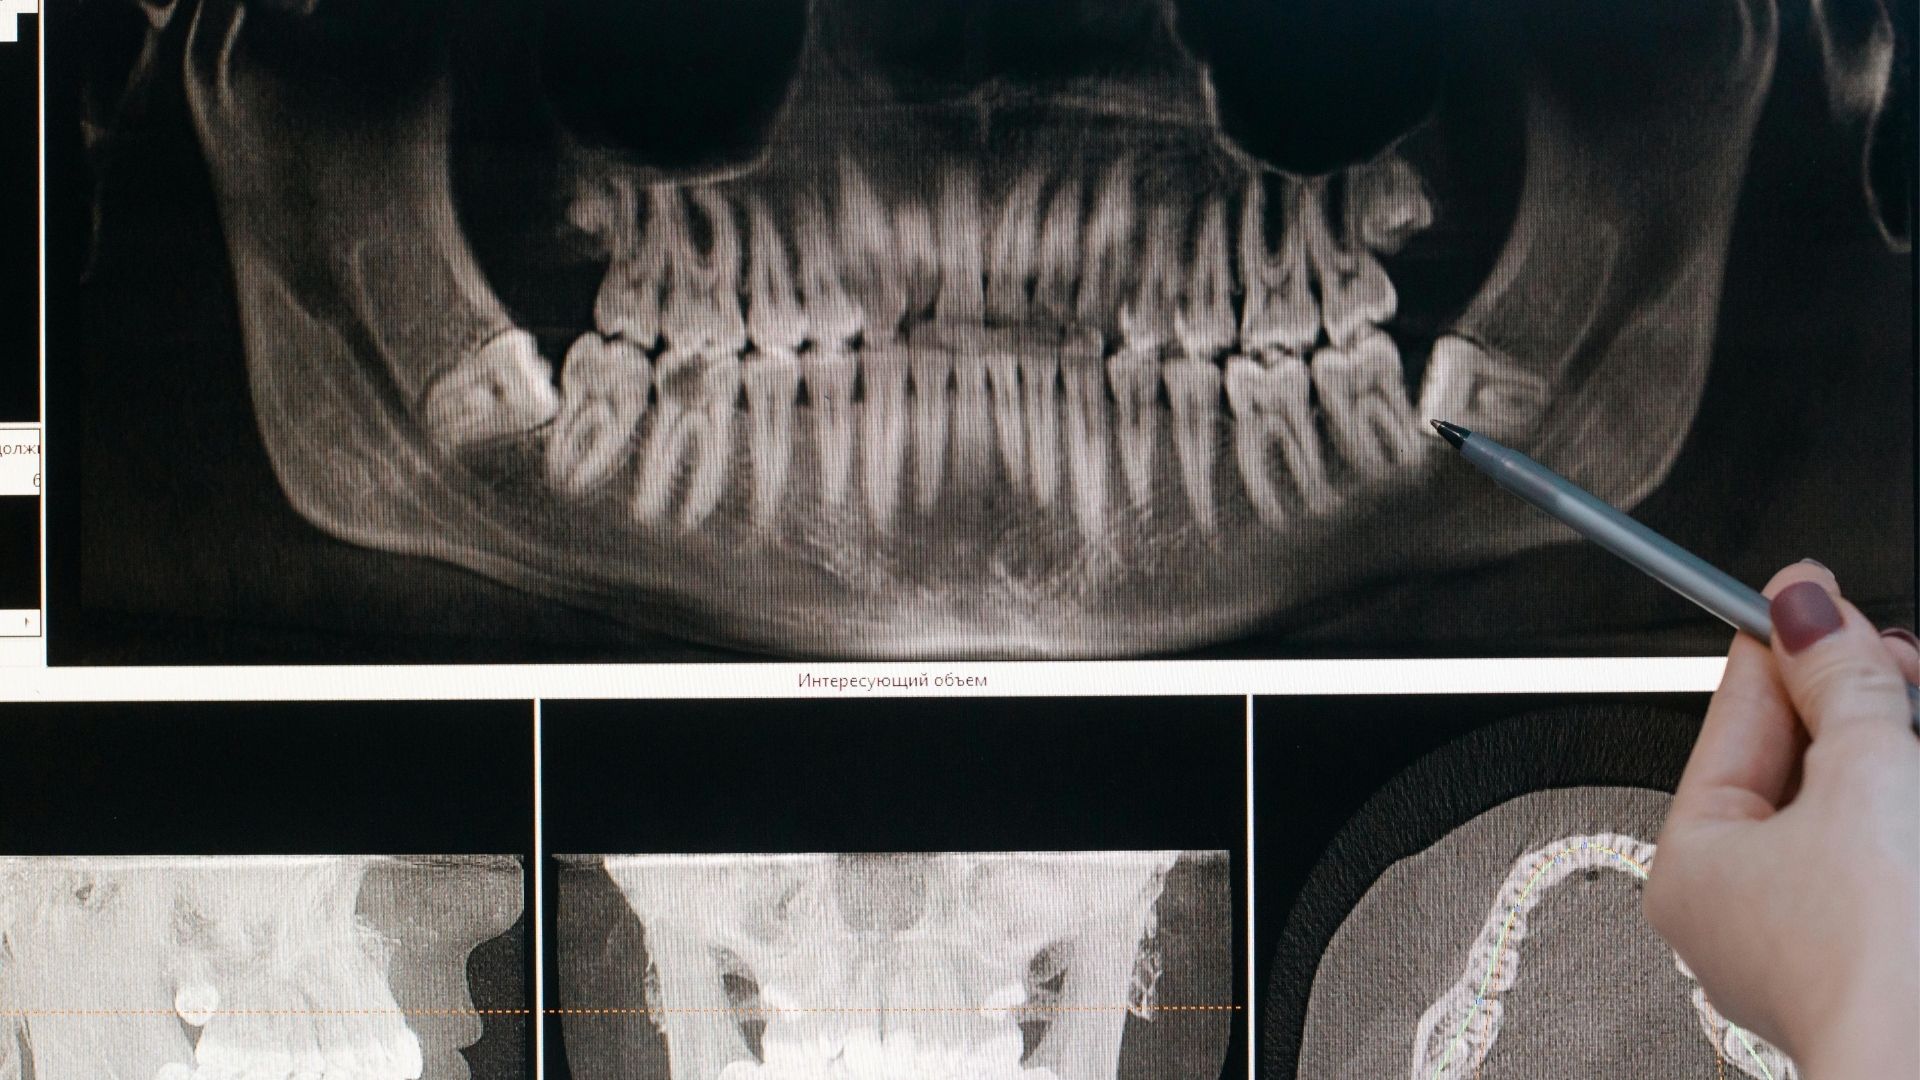

A bölcsességfog eltávolítása akkor válik szükségessé, amikor már teljesen kifejlődött, vagy valamilyen problémát okoz. A fogorvos panoráma röntgen vagy CBCT felvétel alapján határozza meg a beavatkozás szükségességét és típusát. A műtét előtt alapos vizsgálat szükséges, amely során felmérik a fog helyzetét és az esetleges komplikációk lehetőségét. Az időben történő beavatkozás megakadályozhatja a súlyosabb problémák kialakulását és a hosszabb távú kellemetlenségeket.

A bölcsességfog műtét folyamata több lépésből áll, amely biztosítja a beavatkozás sikerességét és minimalizálja a szövődmények kockázatát. Az eljárás a panoráma röntgenfelvétel elkészítésével kezdődik, amely alapján a fogorvos felméri a helyzetet és megtervezi a beavatkozást. A műtét során az ínyt felvágják a fog feltárásához, majd szükség esetén a fogat részekre bontják a könnyebb eltávolítás érdekében. A beavatkozás utolsó lépéseként a sebet kitisztítják és összevarrják, biztosítva ezzel a megfelelő gyógyulást.